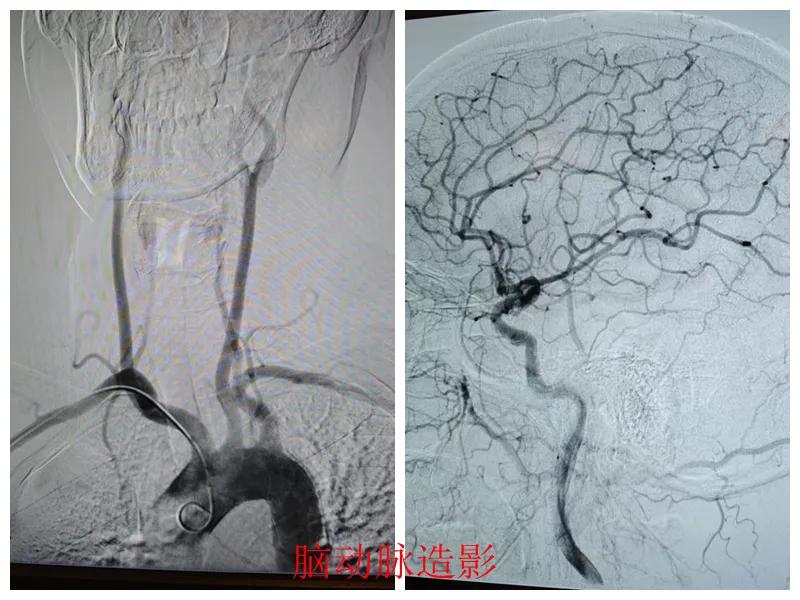

術(shù)前準(zhǔn)備完善后,在王瑾院長帶領(lǐng)下,心血管內(nèi)科主任李慧新、影像科主任宋貴良、副主任醫(yī)師趙進科等緊密協(xié)作,成功為患者實施了冠狀動脈造影及腦動脈造影兩項檢查。冠狀動脈造影結(jié)果提示:患者右冠狀動脈慢性閉塞,腦動脈造影提示腦血管多支狹窄病變。